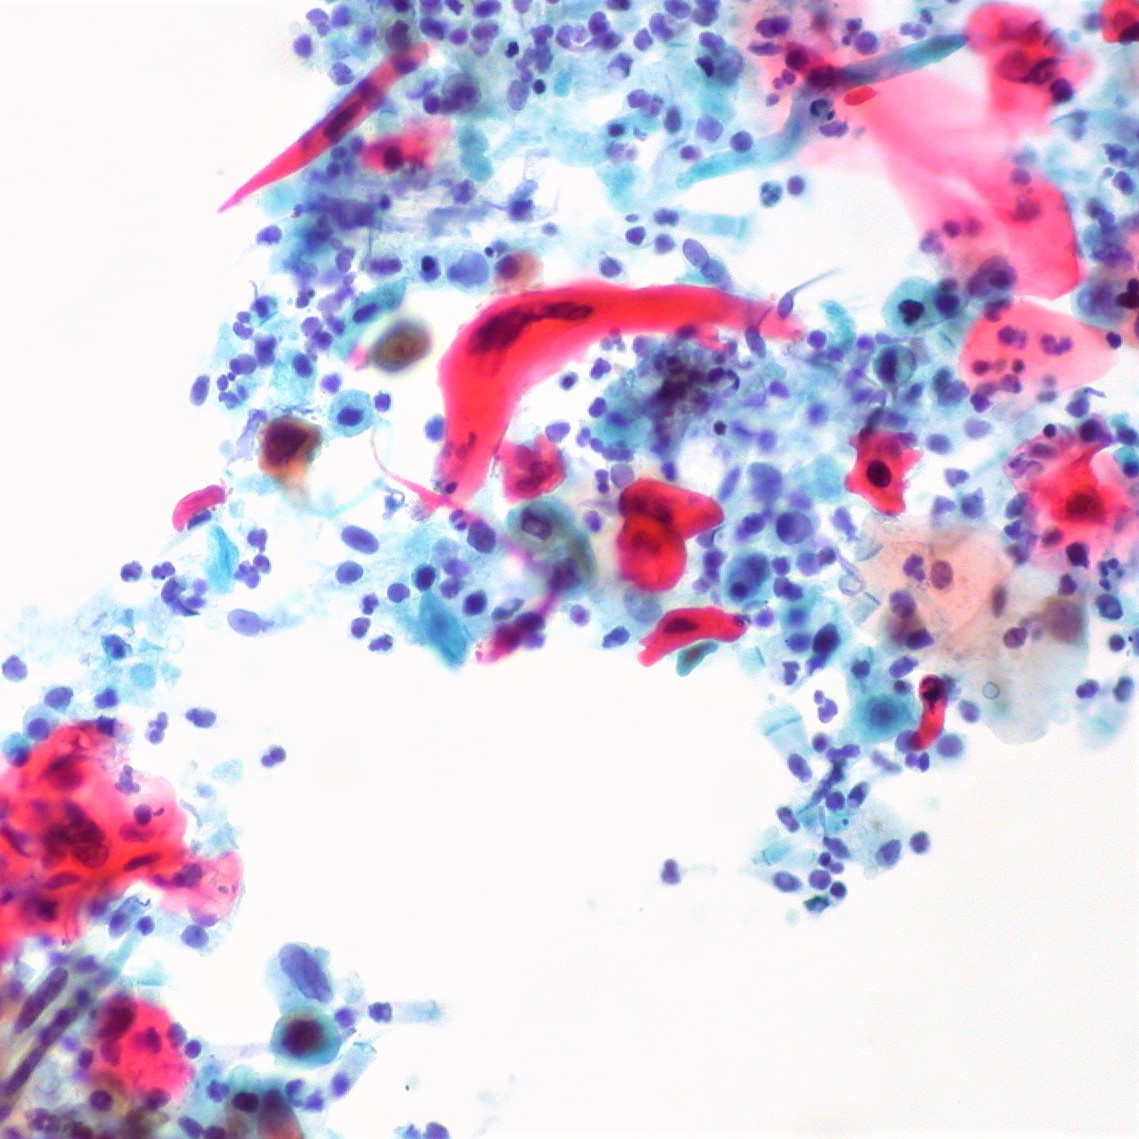

OG-EA31 Pap reagent is alcoholic polychromatic solution. The first step in using the Papanicolaou staining method implies nuclear staining with a hematoxylin solution, and next two steps consist of counterstaining using the monochromatic OG-6 reagent and one of the polychromatic EA reagent formulations. OG-EA31 Pap reagent does not require three, but two steps because it contains OG-6 and EA31 reagents. The Orange G molecule stains the cytoplasm, and in later stages of the procedure it remains only in the mature, keratinized cells. Polychromatic EA31 solution stains non-stained parts of cell, such as squamous cells, nucleoli, ciliary and erythrocytes. Test samples can be gynecological and non-gynecological, such as sputum, urine, and cytological puncture samples. In order to obtain optimal staining results, OG-EA31 Pap reagent has properties completely in compliance with other  reagents for cytological smearing acc. to Papanicolaou – Hematoxylin HP, Pap 1A reagent and Hematoxylin HP, Pap 1B reagent.